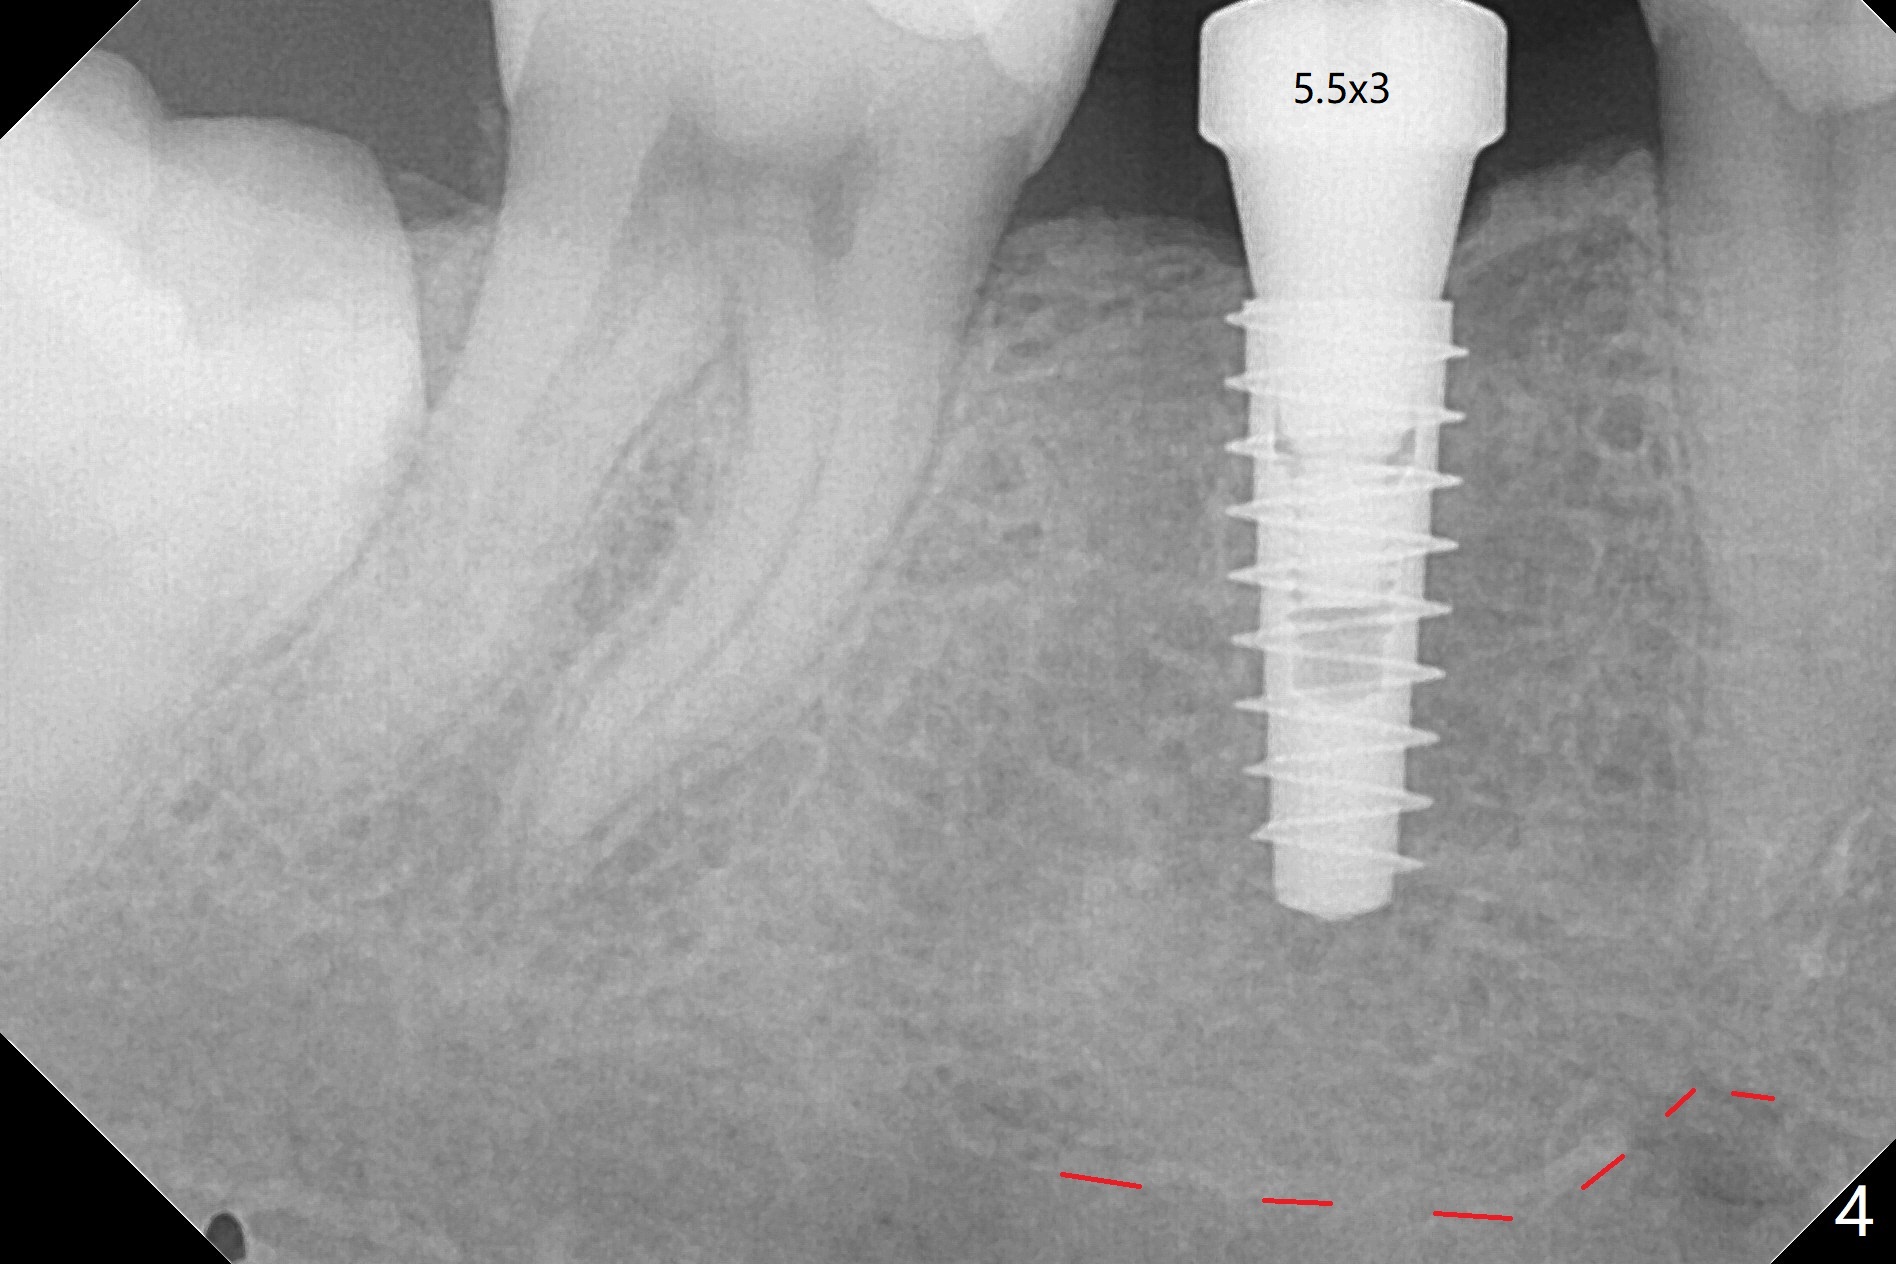

54岁男右下6缺失至少20年,牙槽嵴萎缩,使用导板顺利快速(五分钟)无痛植入4.5x11毫米植体(图一)。使用5.5毫米profile钻头后,放置6x2毫米愈合基台,后者明显没有就位(图二:箭头)。换一个基台,就位好些(图二)。再次使用同一个profile钻头后,可能去除一些近中皮质骨(图二:*),同一个基台完全就位(图三,四(红色虚线:下牙槽神经管上缘)),在愈合过程,基台不太可能脱落了。图一,二使用小sensor,而图三,四:大sensor。尽管使用小钻头(3.5毫米),扭力约20Ncm。